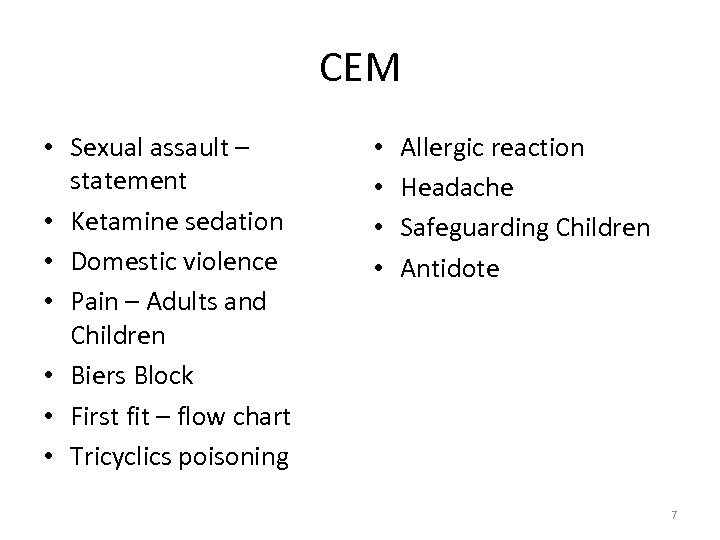

CEM • Sexual assault – statement • Ketamine sedation • Domestic violence • Pain – Adults and Children • Biers Block • First fit – flow chart • Tricyclics poisoning • • Allergic reaction Headache Safeguarding Children Antidote 7